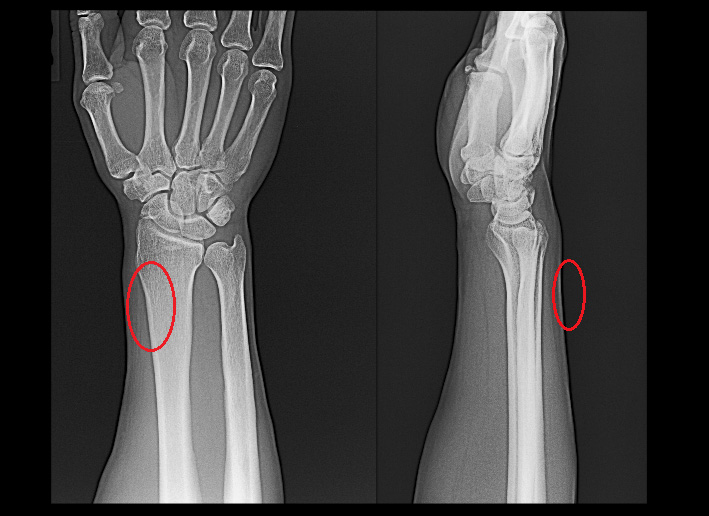

57才男Xp.jpg

57才の男性です。X年12月19日に右手関節近傍に痛みが発症し、その後同部の痛みが悪化し、12月29日に当院を受診されました。右手関節を背屈(手の甲側に屈曲)すると痛みの部位にはあつれき音を触知します。

レントゲンでは異常はありません。